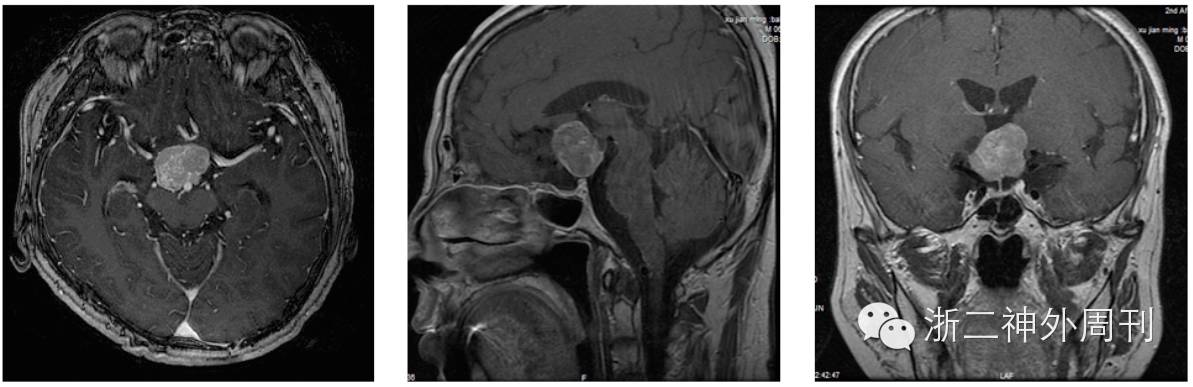

患者1周前当地医院体检,头颅MRI平扫提示:鞍上池占位;双侧基底节脑缺血灶,双侧脑室旁白质脱髓鞘改变。遂来我院进一步诊治。增强头颅MR提示:鞍上池占位,考虑脑膜瘤可能,颅咽管瘤不除外(图1)。

图1. MRI增强示肿瘤位于鞍背上方,与垂体无关。强化明显但欠均匀,边尚清。